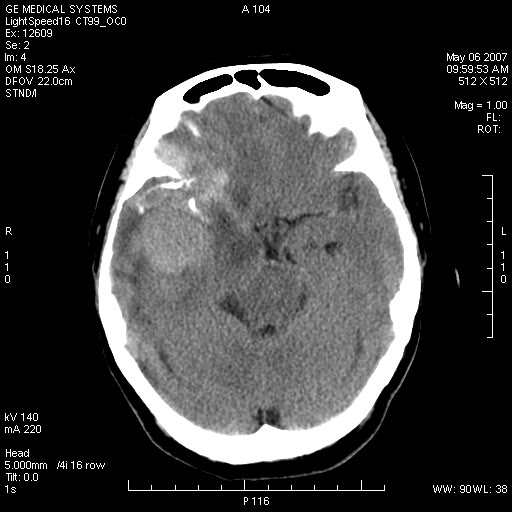

女,60岁,头痛6~7天。

右颞叶巨大高低混杂密度肿块,病灶内可见多发条块状钙化影,占位效应明显,中线结构显著左偏,肿块周围水肿明显,临近颅骨吸收变薄,边缘光整,考虑1少枝胶质瘤2脑膜瘤3转移瘤4室管膜瘤5淋巴瘤6三叉神经瘤(多多益善)合并镰下疝

右颞叶混杂密度,累及右额叶。其内可见条片状钙化及斑片状略高密度,周围少量水肿,右颞骨吸收变薄,中线结构左移。考虑1少突胶质瘤。2脑膜瘤。合并瘤卒中。建议增强扫描。

右额、颞叶巨大高低混杂密度肿块,病灶内可见多发条块状钙化影,占位效应明显,中线结构显著左偏,肿块周围水肿明显,临近颅骨吸收变薄,边缘光整。

考虑:1、少枝胶质瘤;

2、脑膜瘤?

3、镰下疝;

4、建议增强扫描进一步检查。

右额、颞叶巨大高低混杂密度肿块,病灶内可见多发条块状钙化影,占位效应明显,中线结构显著左偏,肿块周围水肿明显,临近颅骨吸收变薄,边缘光整考虑: 1、脑膜瘤;

2、胶母?

4、建议增强扫描进一步检查